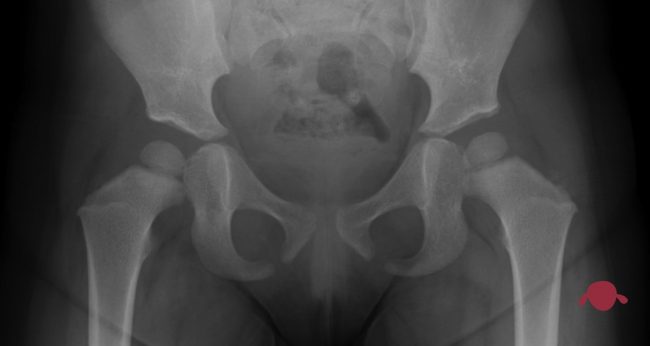

Un yeso pelvipédico o espica de yeso es una escayola que va desde el ombligo hasta los pies. Hay ciertas variaciones: pie incluído, tobillero o “pantalón corto”. Muchos tiene barra entre las piernas, se puede usar para sujetar al niño. Pero todos te complican la vida en cuatro puntos: 1) cambiar el pañal…